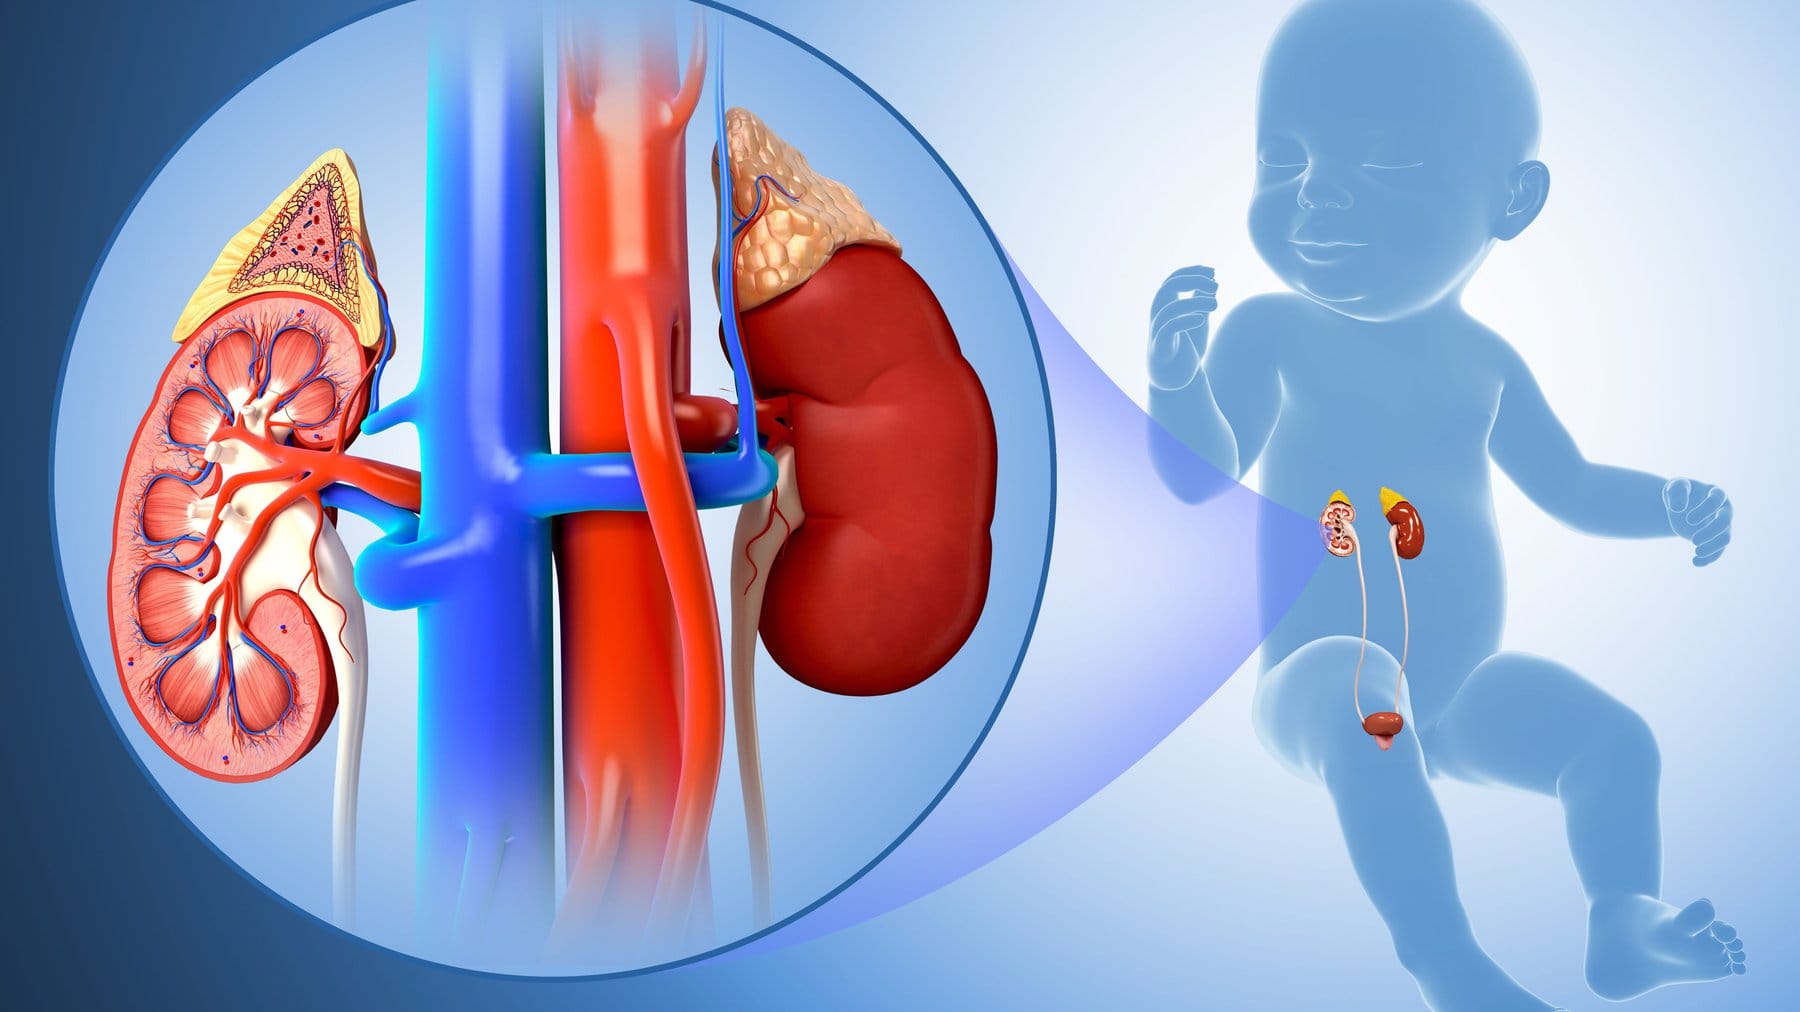

Viêm cầu thận cấp ở trẻ, dự phòng thế nào?

SKĐS - Viêm cầu thận cấp là bệnh do rối loạn miễn dịch, thường khởi phát bởi tình trạng nhiễm liên cầu nhóm A. Bệnh có thể xảy ra ở mọi lứa tuổi, nhưng thường gặp ở trẻ từ 5 - 10 tuổi. Trước đó 2 tuần, trẻ có thể bị nhiễm trùng da, sốt, đau họng... Vì vậy, dự phòng viêm cầu thận cấp là vô cùng quan trọng.

Viêm cầu thận cấp hậu nhiễm liên cầu là nguyên nhân thường gặp nhất của viêm thận cấp ở trẻ em trên toàn thế giới.

Ước tính có trên 470.000 trường hợp mắc mới hàng năm trên toàn thế giới, 97% xuất hiện ở những vùng có tình trạng kinh tế xã hội khó khăn.

Nguy cơ của viêm cầu thận cấp tăng lên với những trẻ từ 5 - 12 tuổi. Trong đó, tỉ lệ viêm cầu thận cấp sau nhiễm liên cầu được phát hiện trên lâm sàng ở những trẻ bị lây nhiễm trong một trận dịch liên cầu nhóm A xấp xỉ là 10% với viêm họng và 25% với nhiễm khuẩn da.